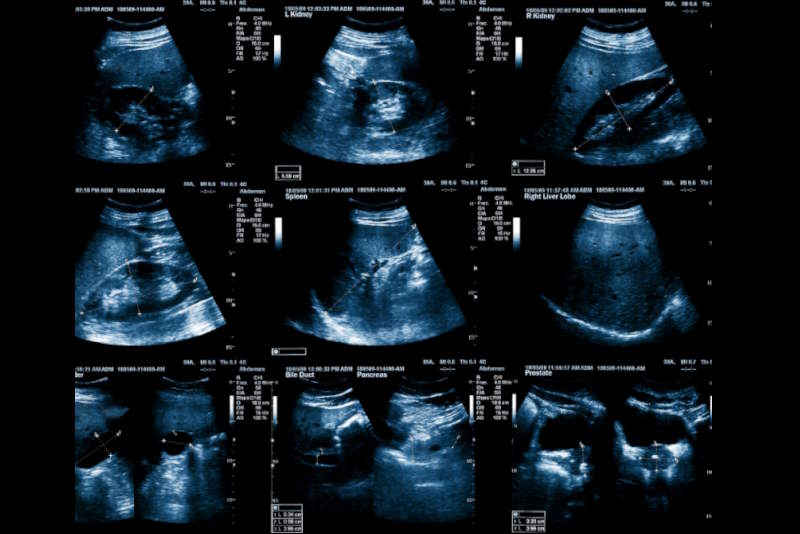

L’ecografia cardiaca, o ecocardiogramma, è un esame non invasivo che consente di osservare in tempo reale la struttura e il funzionamento del cuore. Grazie agli ultrasuoni, il medico può valutare le camere cardiache, le valvole, la contrattilità del muscolo cardiaco e la circolazione del sangue al suo interno.

La procedura è rapida, indolore e non comporta alcuna esposizione a radiazioni. Viene eseguita con una sonda ecografica applicata sul torace e dura generalmente tra i 15 e i 30 minuti.

Durante l’esame, il paziente viene fatto stendere su un lettino, e una sonda ecografica viene fatta scorrere sul torace, con l’ausilio di un gel conduttivo. L’intera procedura è assolutamente indolore e ben tollerata da tutti.